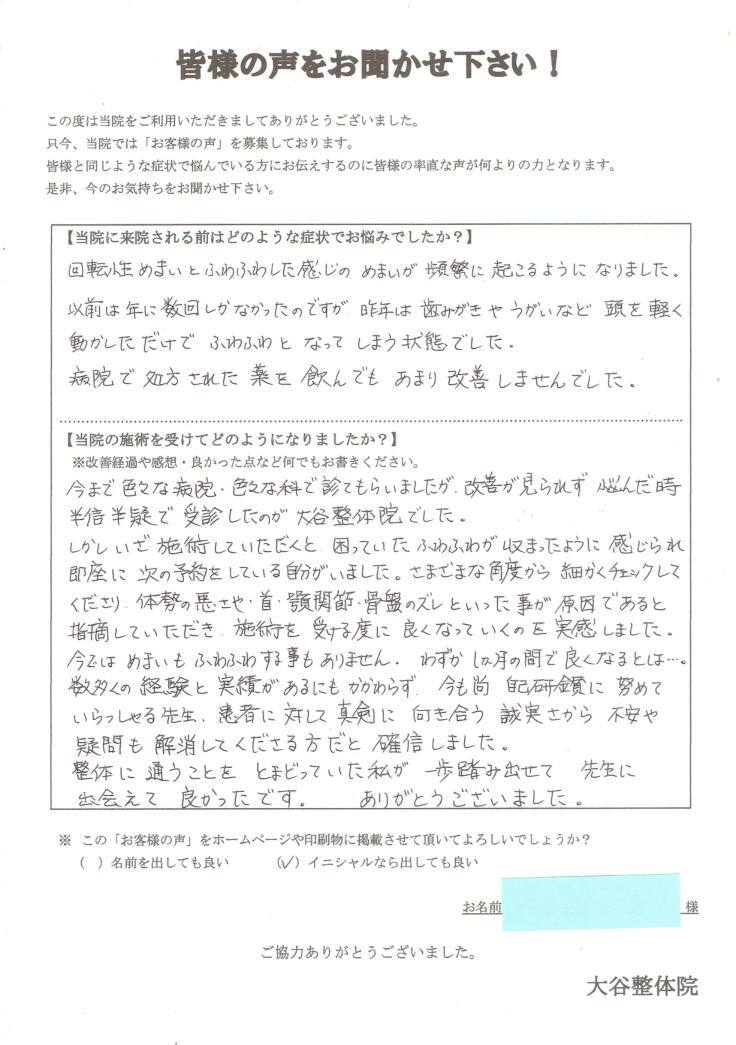

回転性めまいとふわふわした感じのめまいが改善したKさん

当院に来院される前はどのような症状でお悩みでしたか?

回転性めまいとふわふわした感じのめまいが頻繁に起こるようになりました。

以前は年に数回しかなかったのですが、昨年は歯磨きやうがいなど頭を軽く動かしただけでふわふわとなってしまう状態でした。

病院で処方された薬を飲んでもあまり改善しませんでした。

当院の施術を受けてどのようになりましたか?

今までいろいろな病院・いろいろな科で診てもらいましたが改善がみられず悩んだ時に半信半疑で受診したのが大谷整体院でした。

しかし、いざ施術して頂くと困っていたふわふわが治まったように感じられ、即座に次の予約をしている自分がいました。

さまざまな角度から細かくチェックしてくださり、体勢の悪さや首・顎関節・骨盤のズレといった事が原因であると指摘していただき、施術を受ける度に良くなっていくのを実感しました。

今ではめまいもふわふわする事もありません。

わずか1ヵ月の間でよくなるとは…。

数多くの経験と実績があるにもかかわらず、今も尚、自己研鑽に努めていらっしゃる先生、患者に対して真剣に向き合う誠実さから不安や疑問も解消してくださる方だと確信しました。

整体を通うことをとまどっていた私が一歩踏み出せて先生に出会えて良かったです。

ありがとうございました。

※個人の感想であり、効果効能を保証するものではありません。